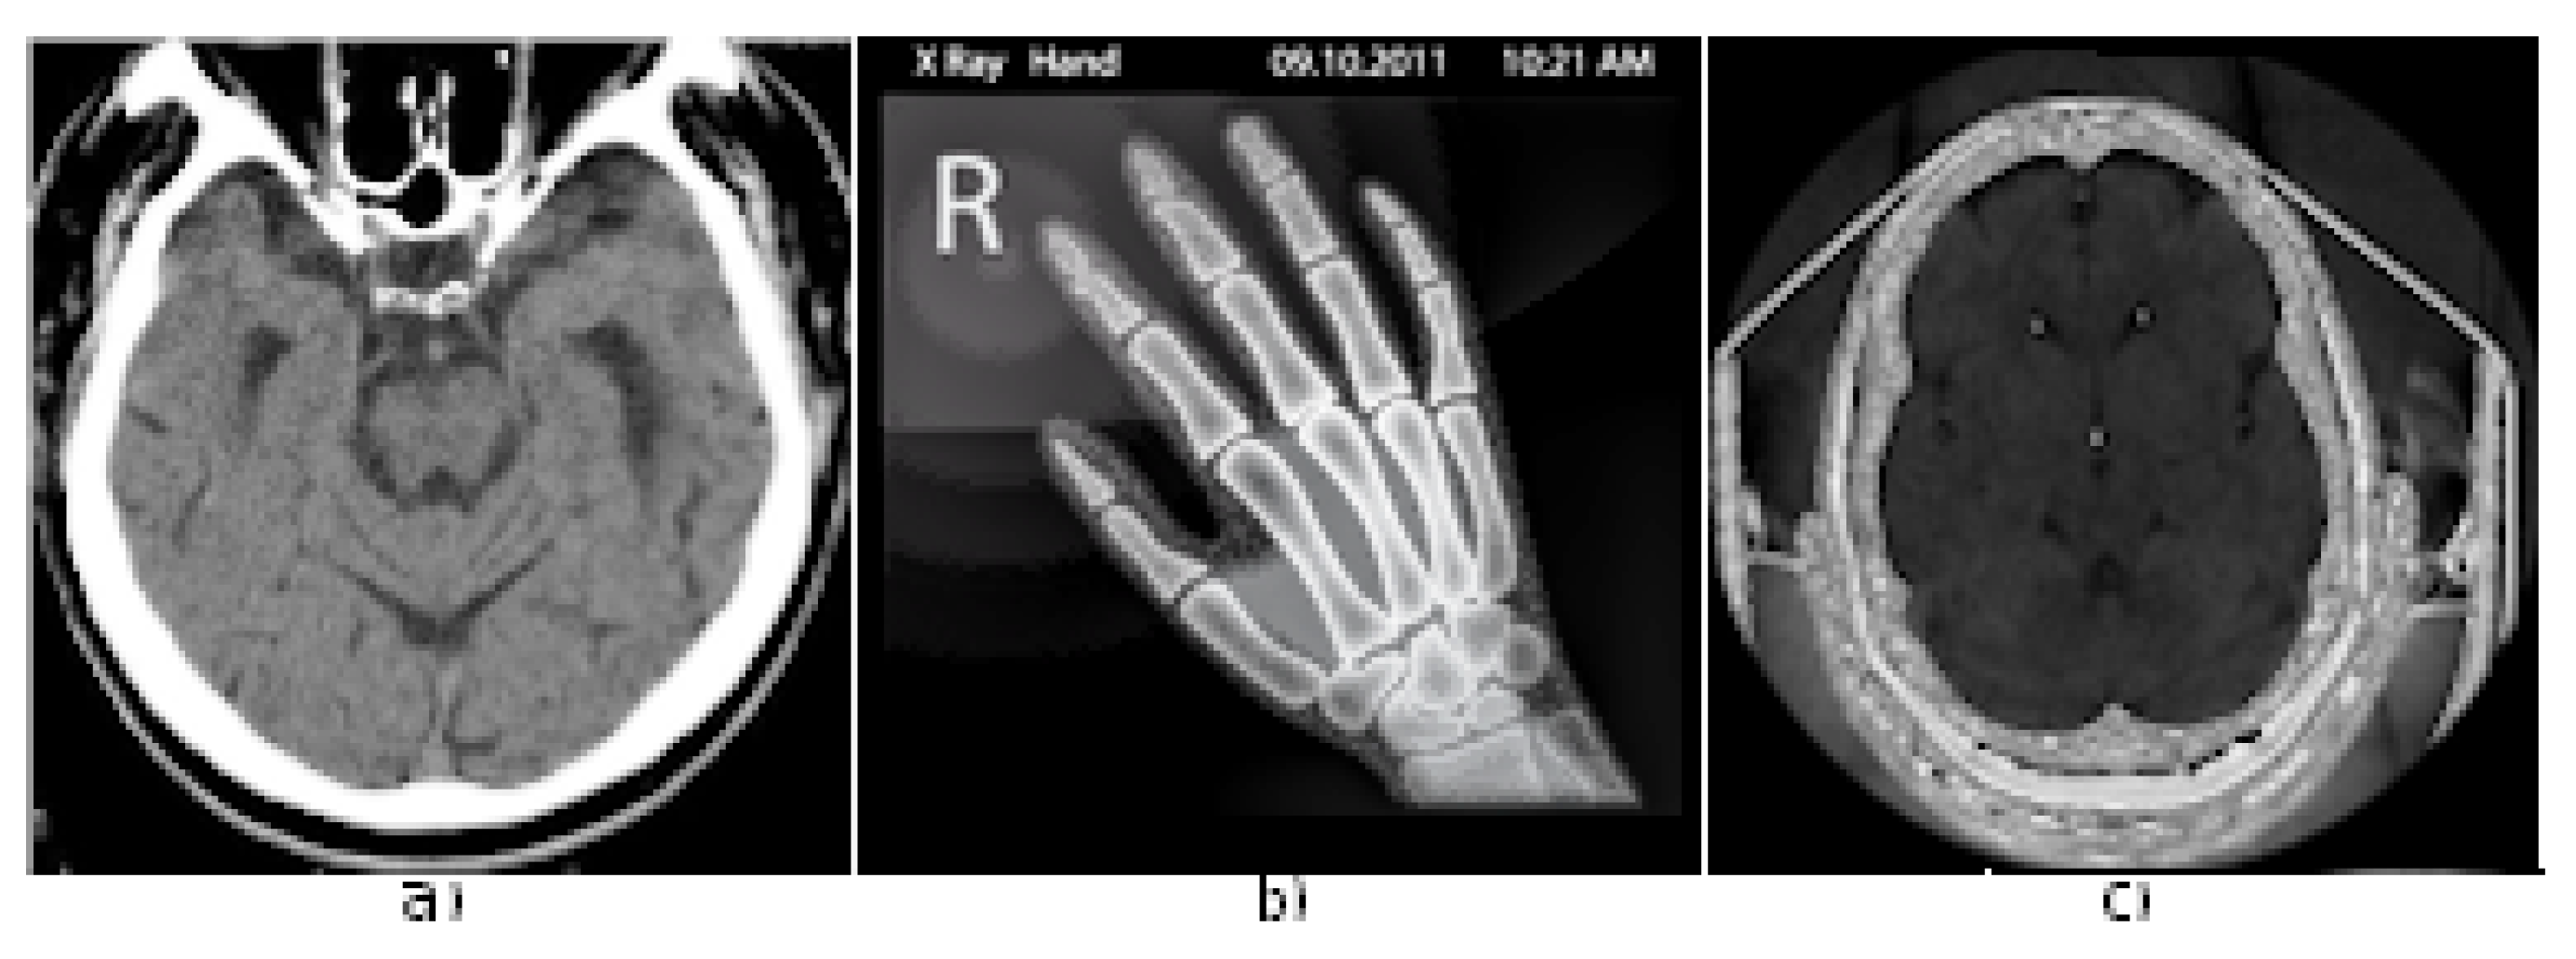

- Data-set. The experimental data set includes the medical images for the experiments as in Figure 3. The current study makes use of four medical images, as shows Figure 3. The medical image Brain CT with 128 × 128 resolution could be provided for free by request from authors for scientific reasons; Hand X-ray from [34] with original 225 × 225 resolution was reduced to 128 × 128 resolution to make a valid comparison with the other images, as Head CT from [35] has originally also 128 × 128 resolution; these two medical-images are available online for free.